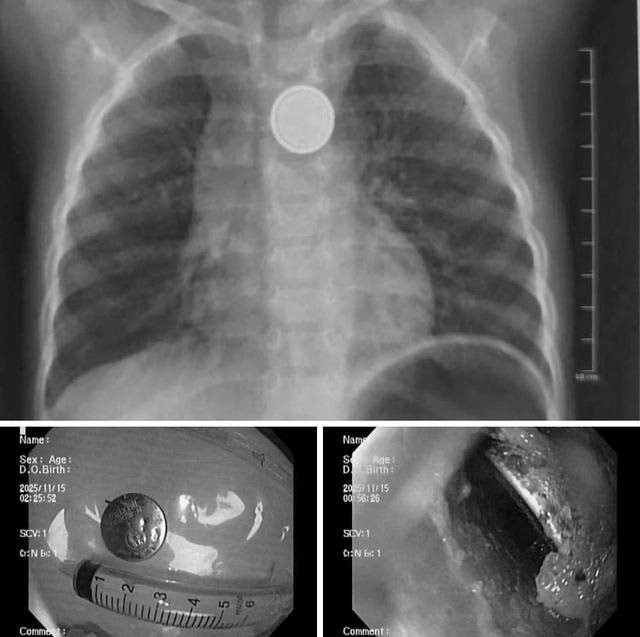

Kết quả X-quang cho thấy dị vật mắc lại ở thực quản. Các bác sĩ tiến hành nội soi cấp cứu và gắp thành công viên pin. Tuy nhiên, quan sát trực tiếp tại vị trí mắc cho thấy vùng thực quản đã bị ăn mòn và loét lớn - minh chứng pin cúc áo có thể gây tổn thương nặng nề chỉ trong thời gian rất ngắn, dù trẻ được đưa đến viện sớm.

Hình ảnh viên pin cúc trong thực quản bệnh nhi. Ảnh: Bệnh viện Nhi Hải Phòng

Hình ảnh dị vật là pin cúc áo trong thực quản trẻ. Ảnh: Bệnh viện Nhi Hải Phòng